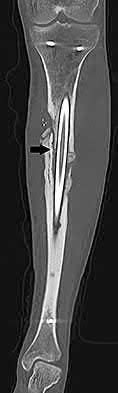

Question 9:

A 72-year-old female on prolonged bisphosphonate therapy presents with thigh pain. Radiographs show a fracture of the femoral shaft. Which of the following radiographic features is most characteristic of an atypical femur fracture associated with bisphosphonate use?

Options:

- Spiral fracture pattern with medial comminution

- Transverse or short oblique fracture line originating at the lateral cortex with localized periosteal thickening (beaking)

- High-energy comminuted fracture with extensive soft tissue damage

- Pathologic fracture through a geographic lytic lesion

- Subtrochanteric fracture with significant medial cortical thickening

Correct Answer: Transverse or short oblique fracture line originating at the lateral cortex with localized periosteal thickening (beaking)

Explanation:

Atypical femur fractures (AFFs) associated with prolonged bisphosphonate therapy have specific major criteria defined by the ASBMR. These include a location anywhere from just distal to the lesser trochanter to just proximal to the supracondylar flare, transverse or short oblique orientation, non-comminuted (or minimally comminuted), and originating at the lateral cortex with localized periosteal or endosteal thickening ('beaking').